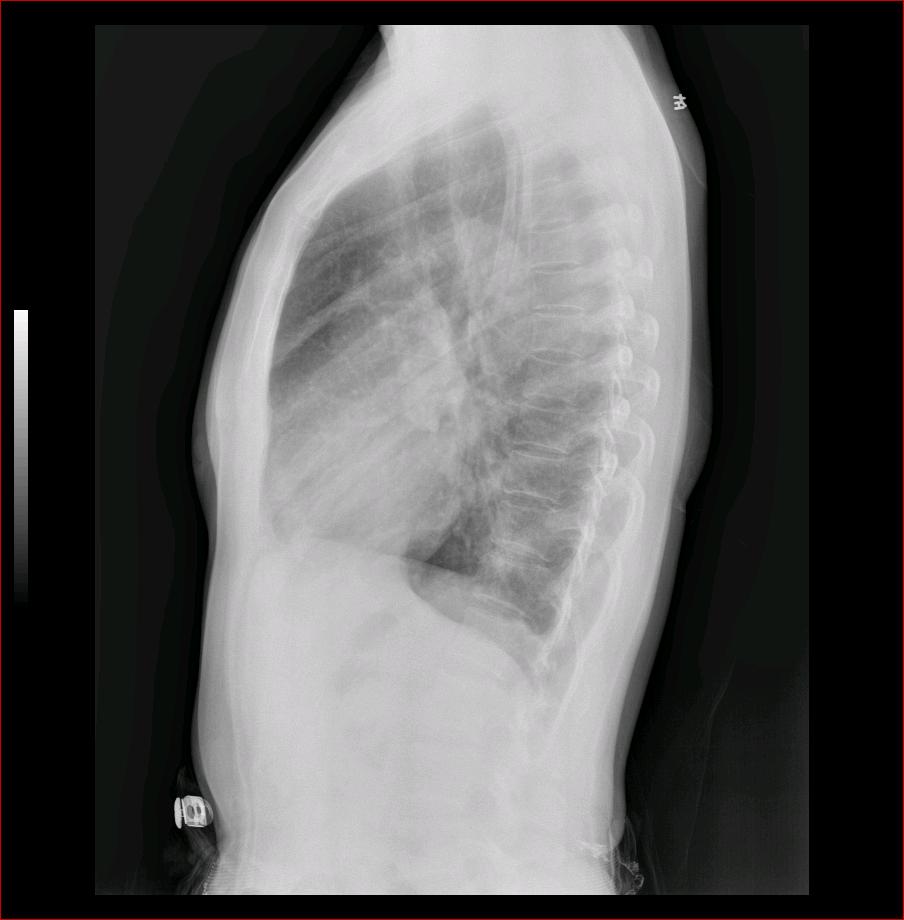

侧位片肺门团块状阴影,考虑左侧中心型肺癌并阻塞性肺炎可能性大,建议ct检查。

侧位见肺门见分叶状肿块影,建议ct进一步检查。

侧位片有提示